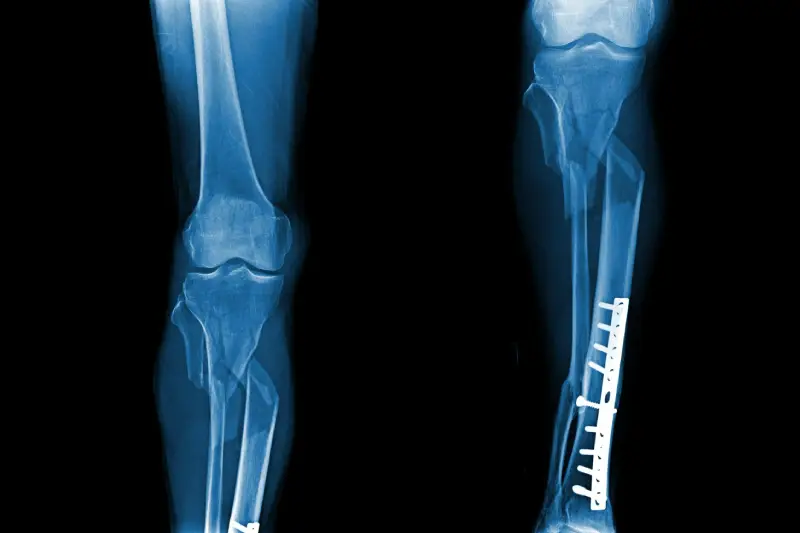

Servicio de retiro de material

El servicio de retiro de material ofrecido por el Dr. Oscar Ignacio Moreno Hernández es una solución efectiva para aquellos pacientes que necesitan retirar material ortopédico o traumatológico de manera segura. Ya sea por complicaciones o por necesidad de una revisión, el Dr. Moreno Hernández cuenta con la experiencia y el conocimiento necesario para llevar a cabo este procedimiento de forma exitosa.